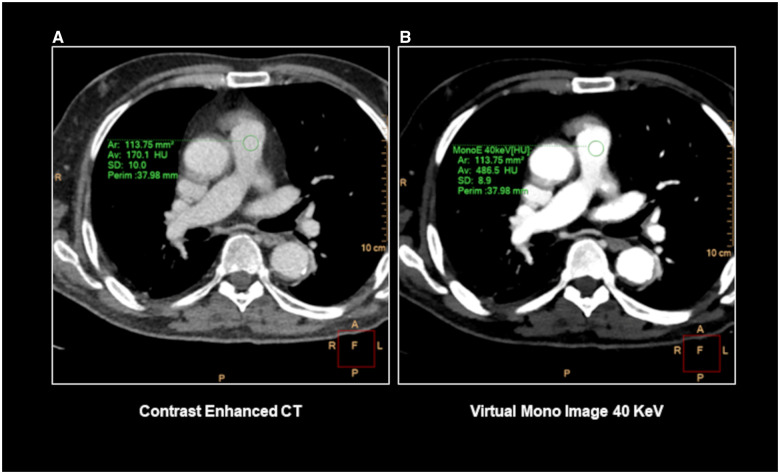

目的:本研究旨在评估利用电子密度(ED)图结合未增强双层双能CT (dl-DECT)扫描胸部获得的z有效(Zeff)图像检测肺栓塞(PE)的可行性。材料与方法:回顾性分析临床怀疑PE或急性主动脉综合征的连续行胸部CT (CECT)增强扫描患者。这些扫描在2021年10月至2023年11月期间在一台dl-DECT扫描仪上进行。为了区分栓子和循环血液,将ED数据集叠加在从未增强阶段获得的Zeff图像上生成彩色编码图。两名具有不同专业水平的放射科医生独立评估了生成的ED-Zeff图中PE的存在,对作为参考标准的CECT结果不知情。对每个阅读器的ED-Zeff图的诊断准确性进行评估。结果:最终研究队列包括150例患者,其中男性92例(平均年龄68±10岁,范围47-93岁),女性58例(平均年龄66±15岁,范围38-89岁)。ED-Zeff图谱表现出较高的诊断性能,准确度、敏感性和特异性分别为86.67% (113/150,95% CI, 80.16%-91.66%)、85% (17/20,95% CI, 79.89%-92.19%)和86.92% (113/130,95% CI, 79.89%-92.19%)。Ed-Zeff图谱能够在85%的阳性病例中识别出PE。Cohen’s kappa系数表明观察者内部和观察者之间的一致性很好(κ≥0.9)。结论:ED图结合未增强dl-DECT扫描的Zeff图像是一种检测PE的可行工具,可能在评估有碘造影剂禁忌症的患者时有用。

Materials and methods: A retrospective analysis was conducted on consecutive patients who underwent for contrast-enhanced chest CT (CECT) clinically suspected of PE or acute aortic syndrome. These scans were performed on a single dl-DECT scanner between October 2021 and November 2023. To distinguish emboli from circulating blood, color-coded maps were generated from the ED dataset superimposed on Zeff images, which were acquired from the unenhanced phase. Two radiologists with different levels of expertise independently assessed the presence of PE in the generated ED-Zeff maps, blinded to CECT results, which served as the reference standard. Diagnostic accuracy of ED-Zeff maps was assessed for each reader.

Results: The final study cohort comprised 150 patients, with 92 males (mean age: 68 ± 10 years, range: 47-93 years) and 58 females (mean age: 66 ± 15 years, range 38-89 years). ED-Zeff maps demonstrated high diagnostic performance, yielding accuracy, sensitivity, and specificity, respectively, of 86.67% (113/150, 95% CI, 80.16%-91.66%), 85% (17/20, 95% CI, 79.89%-92.19%), and 86.92% (113/130, 95% CI, 79.89%-92.19%). Ed-Zeff maps were able to identify PE in 85% of positive cases. Cohen's kappa coefficient indicated excellent intra- and interobserver agreement (κ ≥ 0.9).